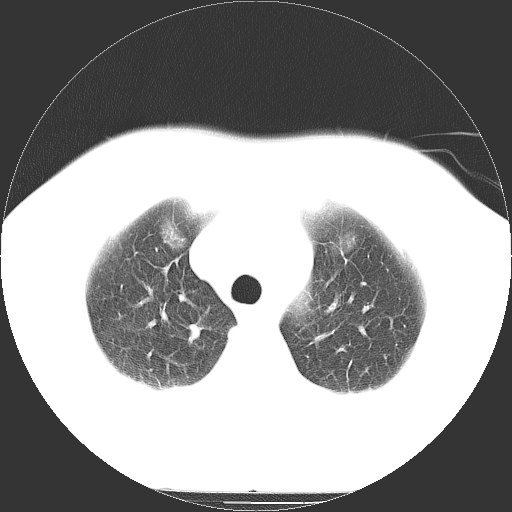

标题: CT21804:男,65岁,咳嗽、咳痰、发热5天。 [打印本页]

男,65岁,咳嗽、咳痰、发热5天。

慢支 肺间质纤维化合并感染!

支气管扩张合并感染,胸膜肥厚

考虑慢支并感染,肺间质纤维化。

两肺间质性炎症并感染

两肺间质纤维化,支扩合并感染,双侧胸腔积液

支持慢性支气管、肺间质纤维化合并感染。

慢性支气管炎并感染,支扩,双侧少量胸腔积液.